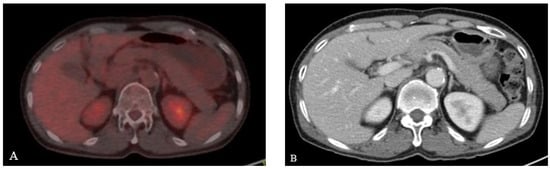

After being diagnosed with acute pancreatitis, the patient fasted for therapeutic purposes and underwent EUS to identify the cause. The echogenicity of pancreas parenchyma was mildly decreased, but there was no lesion with different echo levels in the whole pancreas. Main pancreatic duct did not dilate (Figure 3A) and there was no obstructive maneuver on the papillary side. Stones or sludge within gallbladder was not observed (Figure 3B), and common bile duct did not show dilatation (Figure 3C). In order to determine if the acute pancreatitis occurred due to pancreas involvement of ENKTL or L-asparaginase, we performed EUS -FNB using 25-gauge needle (Acquire, Boston Scientific Corp., Natick, MA, USA) (Figure 3D).

Figure 3.

Endoscopic ultrasonography (EUS) findings. (A) Main pancreatic duct does not dilate with mild decreased echogenicity of pancreas parenchyma. (B,C) Observed gallbladder and common bile duct is unremarkable. (D) EUS-guided fine needle biopsy is performed at the tail of the pancreas.